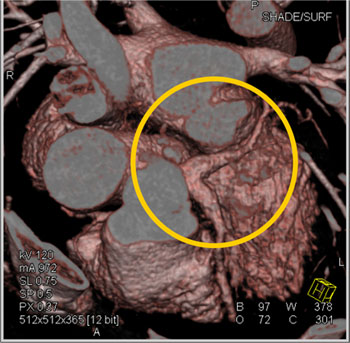

Aneurysm of Circumflex Coronary Artery 27 year old female with symptoms of increasing fatigue and pulsation in the left chest and neck. CTA demonstrates a persistent left SVC and aneurysm of the circumflex coronary artery.

Dx-Aneurysm of the Circumflex Coronary Artery In this patient the cause of the coronary artery aneurysm was atherosclerotic disease and could best be managed by surgical intervention. The patient ultimately decided against any intervention.